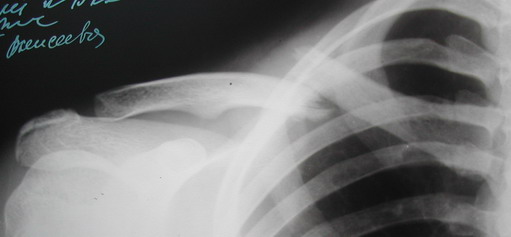

Уважаемые коллеги, а нас очень интересуют вопросы оперативного лечения переломов ключицы. мы пробовали многие варианты (гвоздь Богданова, спицы + Дезо, пластины LCP, LC-DCP, DCP, реконструктивные разных фирм) и, как ни

странно, пришли к БИОСу. Наверное Вы все обратили внимание, что многие известные оперативные методики нашли свое применение в лечении этой "простой" травмы.

Огромное разнообразие переломов этой зоны и сложная геометрия поверхности кости с учетом конституциональных особенностей пациентов и разнообразия выполняемых ими видов деятельности придают планированию оперативного лечения этой области огромное значение: например скромный, адинамичный, неспортивный молодой человек "ботаник" - вполне уместно наложить ватно марлевые кольца или выполнить несложный остеосинтез спицей и заковать пациента в пластиковое ДЕЗО на 3-4 нед. А если перед Вами современный яппи, атлетического телосложения, не желающий в жару находиться в тяжелой повязке и имеющий необходимость продолжать трудовую деятельность сразу же после операции, или он увлекается современным экстримом,,,,,,,, Все это заставляет нас продолжать поиск оптимальных видов оперативного лечения данной области.

В приложении проект наших тезисов на съезд и клинический пример: Пациентка 23 лет поле неэффективного оперативного лечения (4 нед.) перелома ключицы спицей (была оперирована в С-Петербурге)(снимок после удаления спицы) и результат закрытого БИОС..